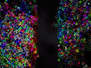

The dentate gyrus is a part of the brain that contributes to the formation of memories. In individuals with Alzheimer’s disease, this is the first site known to undergo degenerative changes even before symptoms start to show. This sounds promising for detecting Alzheimer’s earlier, but this structure is only a few millimetres thick and hidden deep within the brain. To exploit this knowledge, we would need really powerful imaging techniques to detect microscopic changes. Here, researchers used a 16.4 Tesla MRI scanner – a much stronger magnetic field than currently used for human body imaging – to measure changes for example in neuron density and abnormal protein accumulation within the dentate gyrus from postmortem brains of cognitively normal individuals (left) and those with Alzheimer’s (right). Colours highlight neuron fibres in subregions, revealing differences. While this technology is far from ready for a clinical setting, it is a step in the right direction.